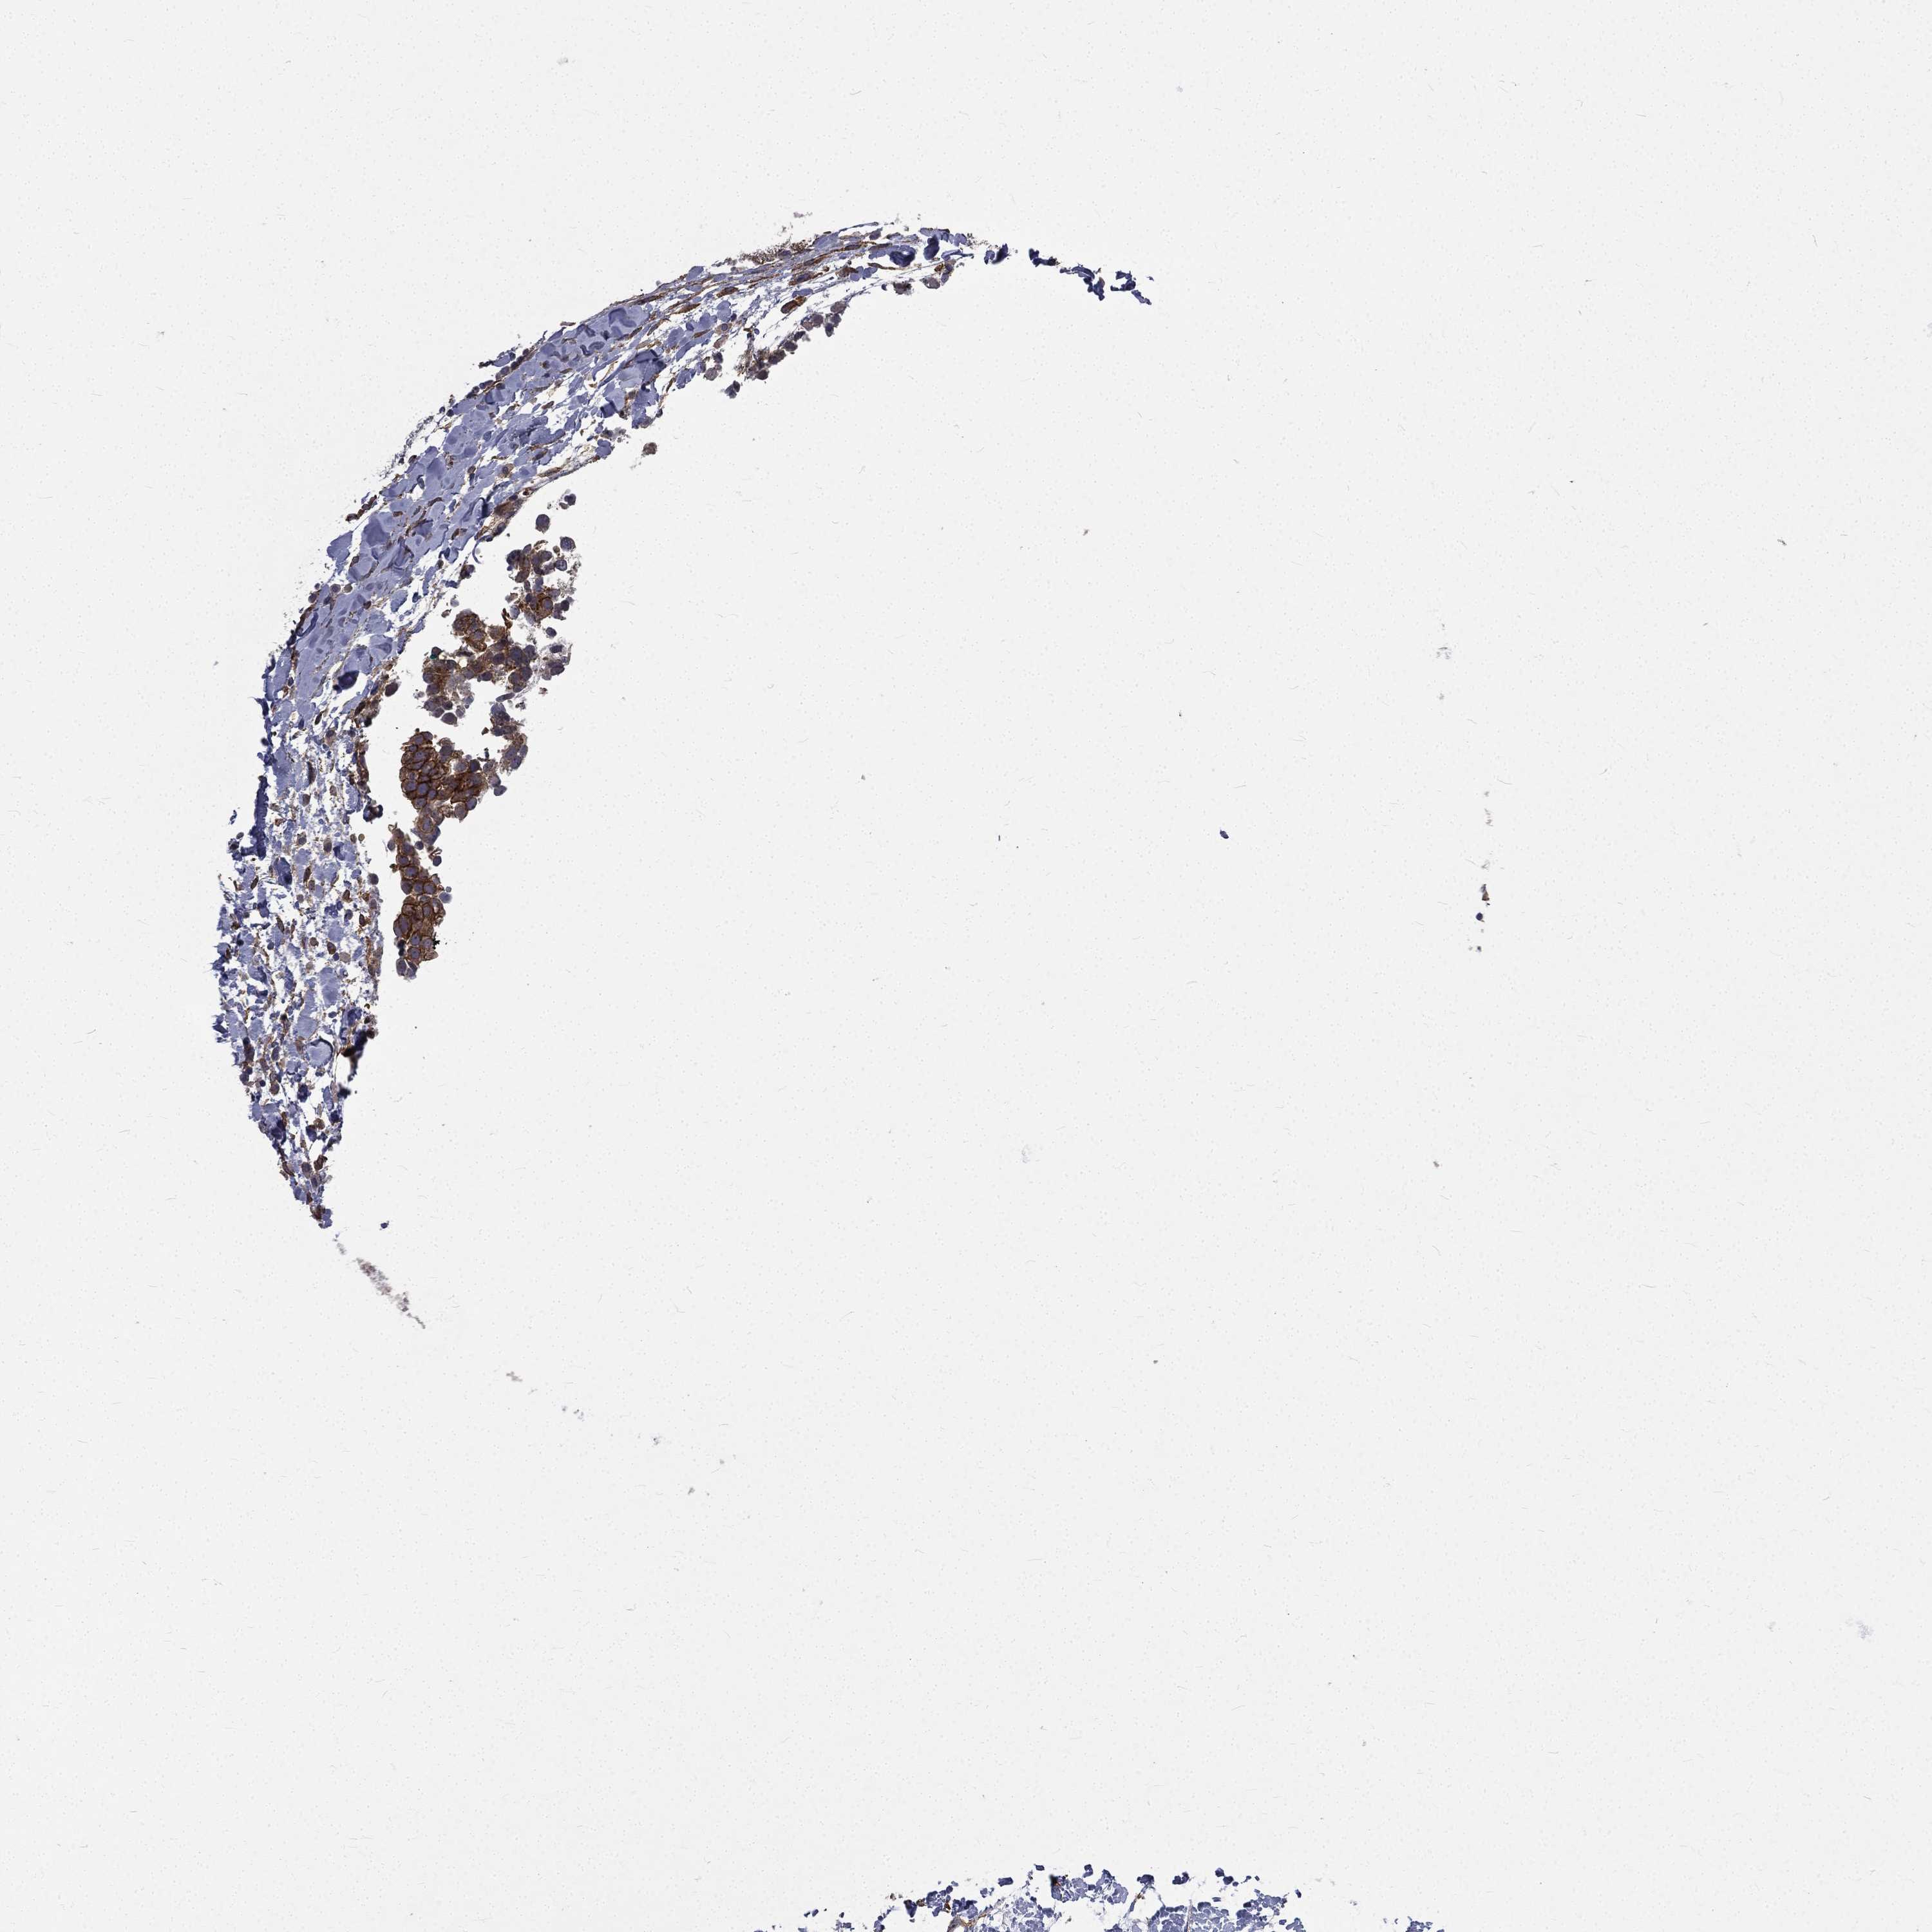

BRCA TCGA BRCA VALIDATION PROTEIN EXPRESSION